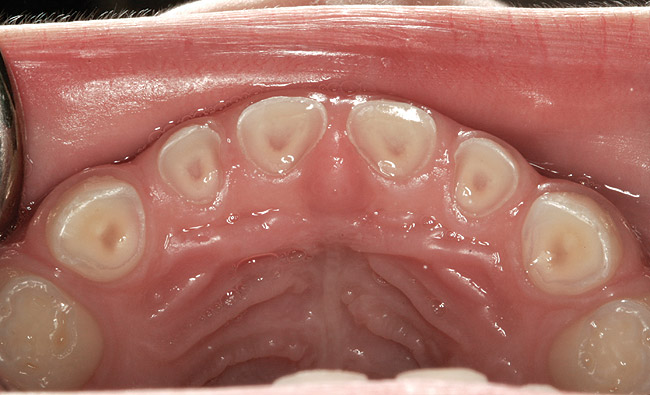

(10.) Narrow maxilla with tooth wear and bilateral crossbite.

Figure 10